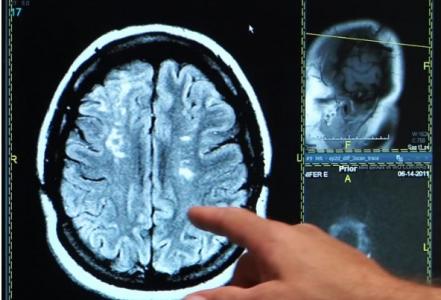

C’est précisément le lien possible entre la consommation de boissons light à base d’édulcorants et les risques d’accident vasculaire cérébral et de démence, qu’analyse cette étude américaine à partir des données de la fameuse Framingham Heart Study. Des conclusions présentées dans la revue Stroke qui, si sur la durée, n’identifient pas d’association significative, suggèrent en revanche sur le court terme qu’une consommation récente de boissons « artificiellement sucrées » est bien liée au risque d’AVC

Ce lien signalé entre les boissons light, la démence et les accidents vasculaires cérébraux reste faible, cependant il ajoute aux préoccupations soulevées par les édulcorants depuis de nombreuses années.

Selon les auteurs, le risque est faible, mais bien là. La consommation de boissons gazeuses artificiellement sucrées est associée à un risque accru d'accident vasculaire cérébral et de démence. Avec des réserves, car même dans cette large étude, le nombre de nouveaux cas d'AVC et de démence est faible, soit respectivement 3% et 5% de la cohorte.